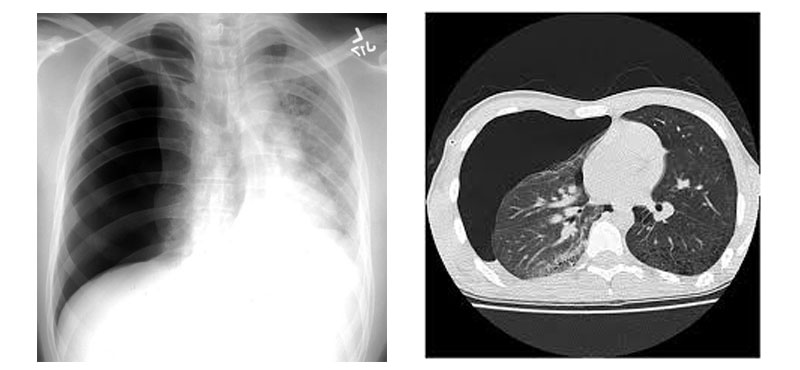

Chest X-ray. CT Thorax once lung has expanded spontaneously or after Intercostal drain (Pig-tail catheter) insertion